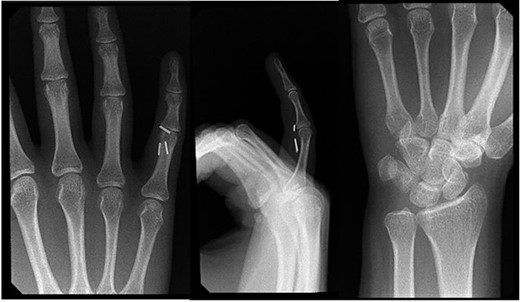

Right hand imaging 1-month status post revision CTR demonstrating hemoclip placement with initial asymptomatic migration of a single clip to the small finger proximal interphalangeal joint.